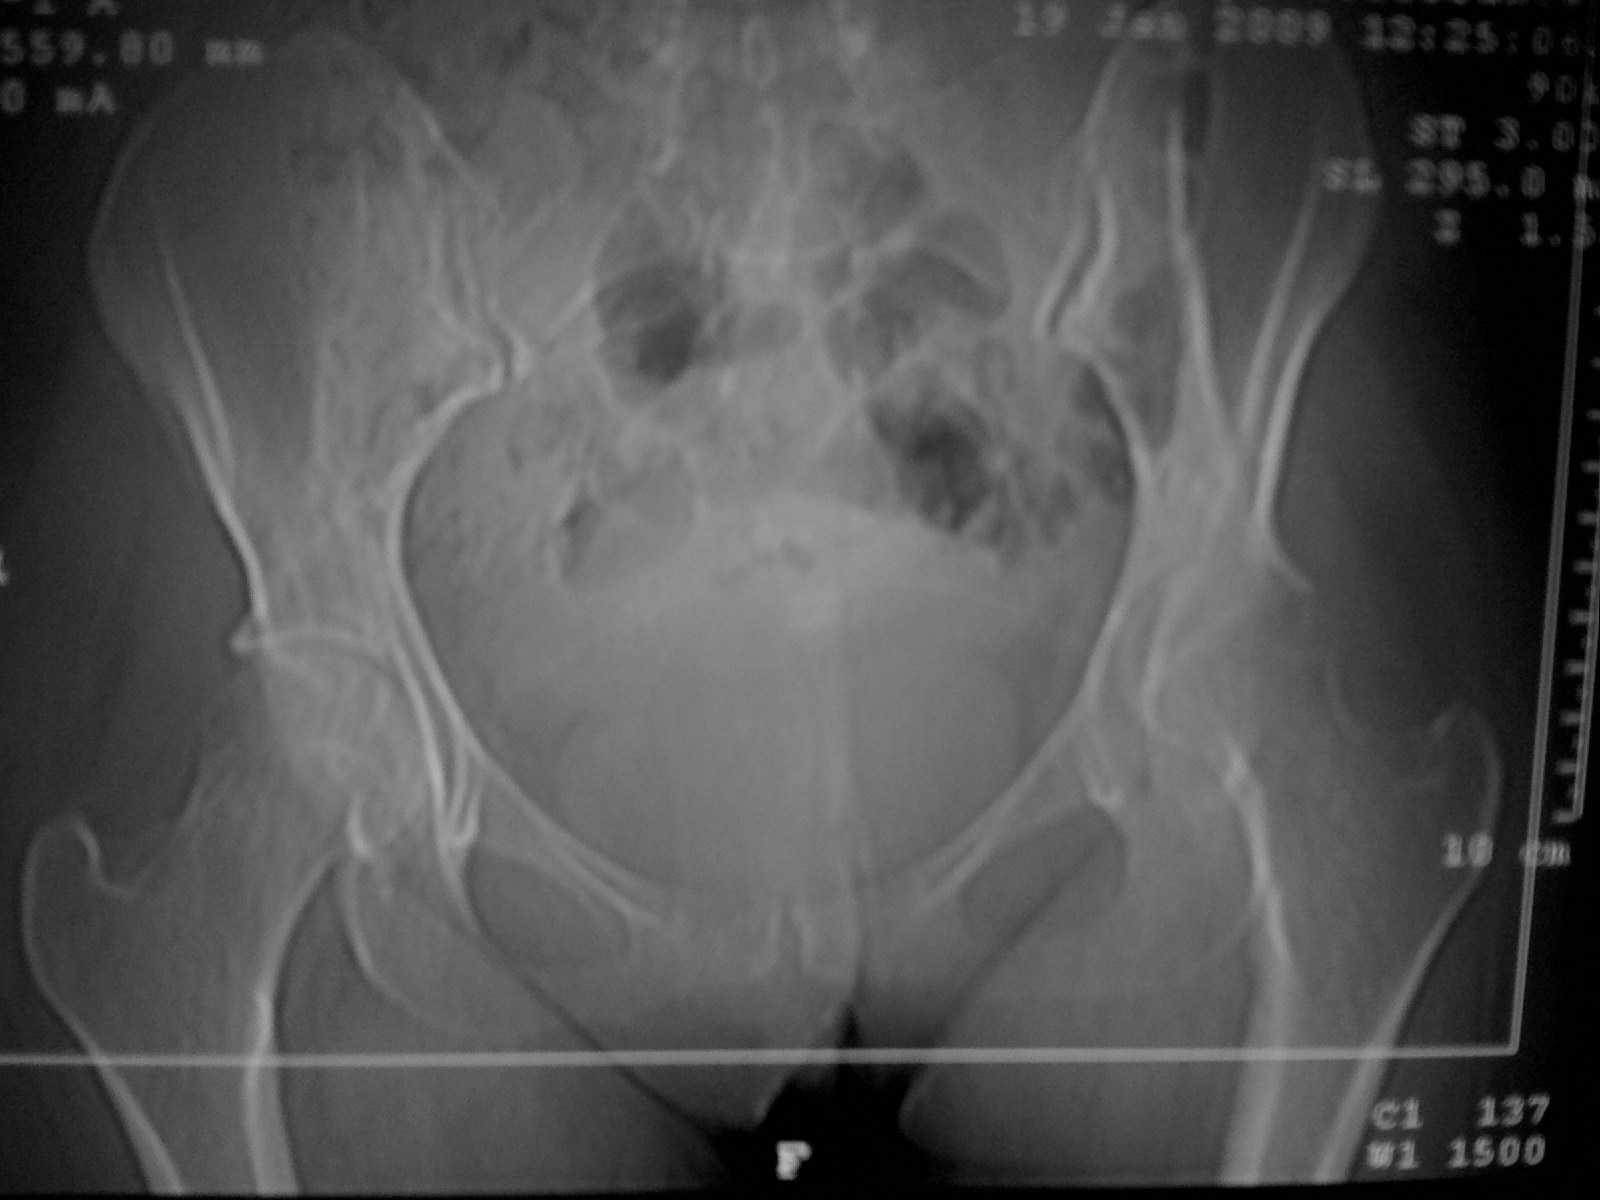

Коллеги! Пациентка 27 лет. Впервые обратилась 6 мес.назад после родов расхождение лонного сочленения, проведена консервативно.

Через 3 мес.повторное обращение по поводу болей в т\б суставе.Ходит с костылями, отведение, приведение в суставе в пределах 10*.Укорочение н\конечности на 3,0см.Непонятен механизм развития данной ситуации и какой метод лечения выбрать. Если протез то какой?